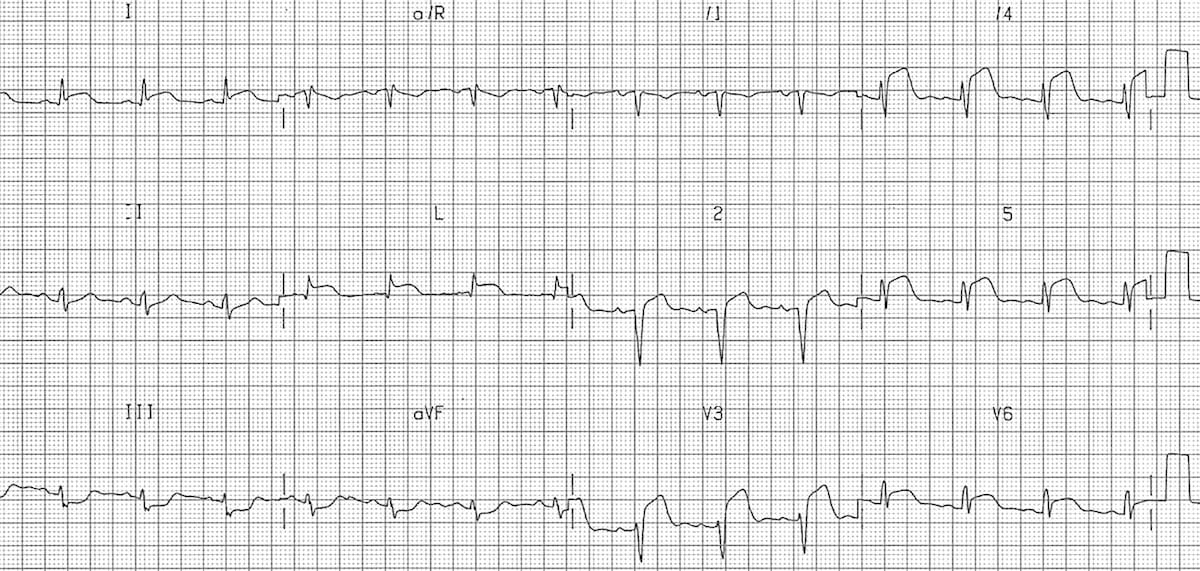

This ECG shows left axis deviation. Applying the thumb rule: lead I is up (+ve) and lead aVF is down (-ve). The left axis deviation is secondary to left ventricular hypertrophy.

© Life in the Fast Lane. Licensed under CC BY-NC 4.0

This ECG shows right axis deviation. Applying the thumb rule: lead I is down (-ve) and lead aVF is up (+ve). The right axis deviation is secondary to right ventricular hypertrophy (from cor pulmonale).

https://litfl.com/top-100-ecg-cases/

© Life in the Fast Lane. Licensed under CC BY-NC 4.0